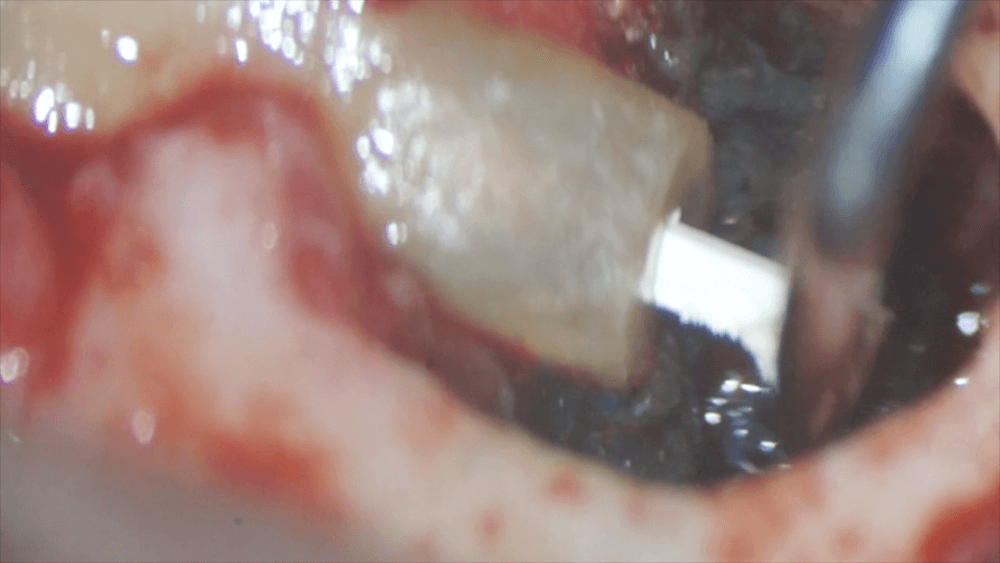

取り残した汚れがないことを確認したら、今度は、根の先から、薬をつめるための器作りを行います。

その器の中に、MTAセメントと呼ばれる材料を入れます。

この後、歯茎を縫い、終了です。